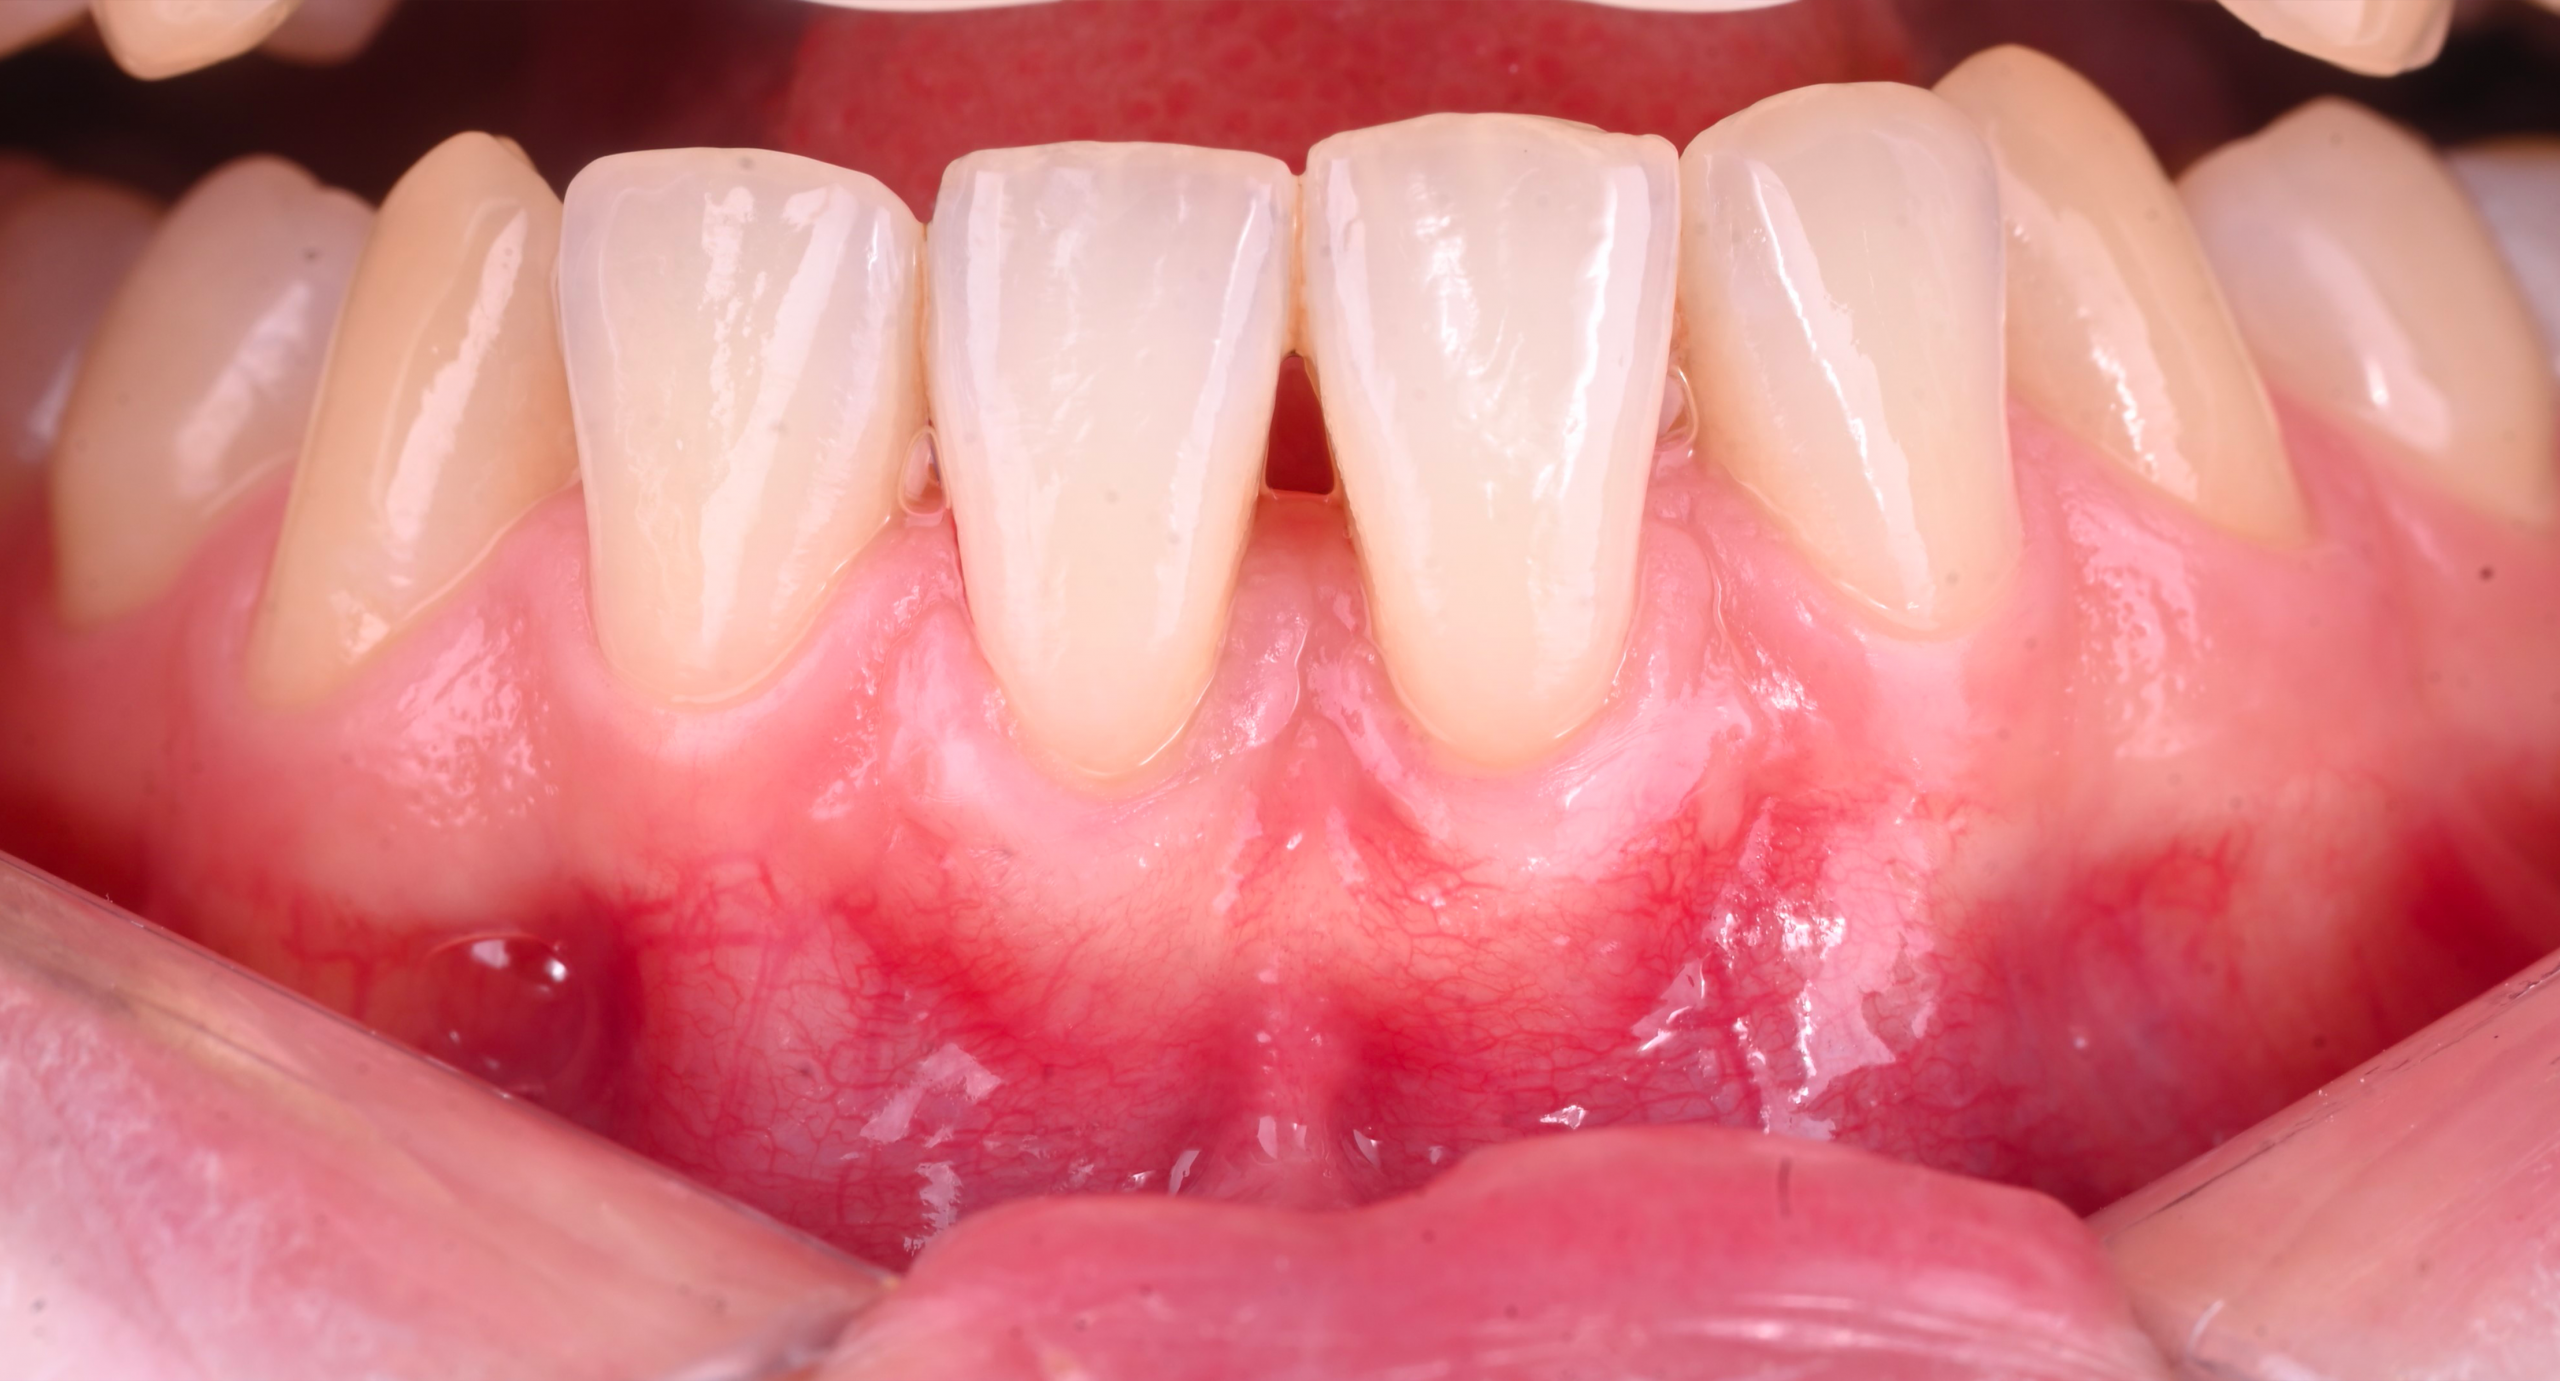

La récession gingivale correspond à un retrait progressif de la gencive qui expose la racine de la dent. Cela peut provoquer :

Une sensibilité accrue au chaud et au froid.

Une gêne esthétique (dents plus longues).

Un risque de caries radiculaires ou de perte d’attache.

Une fragilité osseuse à long terme.